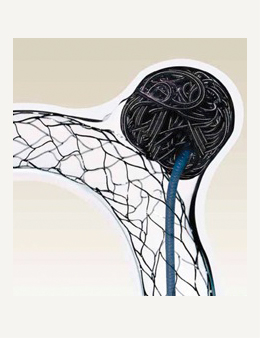

코일색전술은 미세도관을 삽입하여 동맥류 내부로 진입하여 동맥류 내에 백금으로 만든 코일을 삽입하여 동맥류 파열을 막는 치료 입니다.

뇌동맥류를 코일과 스텐트를 이용하여 막은 모습